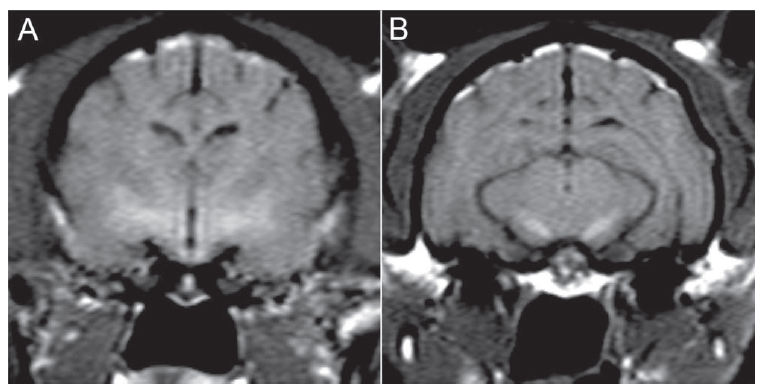

Which disease can cause bilaterally symmetrical T2 hyperintensity in the white matter tracks adjacent to the thalamus?

c) hypernatraemia

wine glass sign